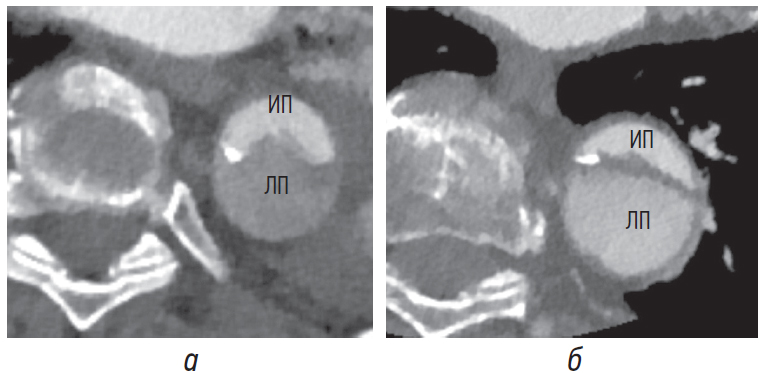

При наличии кальцинатов на лоскуте они обращены в сторону истинного просвета, поскольку ложный просвет в ходе расслоения формируется под ними. Сторона лоскута, обращенная к ложному просвету, имеет мягкотканную плотность без видимых обызвествлений [8], однако этот признак возможно увидеть в том случае, если интимомедиальный лоскут достаточной толщины (рис. 10, а, б).

Рис. 10. Интимомедиальный лоскут при хронической диссекции утолщен и уплощен с наличием отчетливо визуализируемых на его фоне кальцинатов (стрелки) со стороны истинного просвета. Со стороны ложного просвета стенка лоскута имеет мягкотканную плотность. ИП — истинный просвет, ЛП — ложный просвет

Кальциноз стенки аорты

Еще одним важным признаком, позволяющим дифференцировать истинный и ложный просветы, является кальциноз стенки аорты в области диссекции. При острой диссекции кальциноз стенки аорты всегда указывает на истинный просвет (рис. 11, а) и никогда не определяется в ложном просвете. Однако при хронической диссекции этот признак не настолько надежен, потому что стенка ложного просвета хотя и намного реже, но также может быть обызвествлена (рис. 11, б). При этом кальциноз стенки ложного просвета наблюдается только при хронических диссекциях, что связано с ее эндотелизацией и последующей кальцификацией. Также отсутствие кальциноза внешней стенки со стороны эксцентрично расположенного тромба помогает отличить тотально тромбированный ложный просвет при аортальной диссекции от пристеночного тромба аневризмы аорты [4, 5, 7, 8].